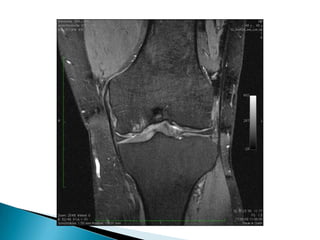

5) Manejo del Ultrasonido general en el diagnóstico de los reumatismos de partes blandas.6) Asesores en la utilización racional de métodos diagnósticos como resonancia o artroscopias e indicaciones quirúrgicas para pacientes reumáticos, que son prescritas con mucha mayor ligereza por parte de otros especialistas de áreas afines.7) Supervision y regulacion de la terapia física y ocupacional administrada a enfermos reumáticos.

5) Manejo delUltrasonido general en el diagnóstico de los reumatismos de partes blandas.6) Asesores en la utilización racional de métodos diagnósticos como resonancia o artroscopias e indicaciones quirúrgicas para pacientes reumáticos, que son prescritas con mucha mayor ligereza por parte de otros especialistas de áreas afines.7) Supervision y regulacion de la terapia física y ocupacional administrada a enfermos reumáticos.